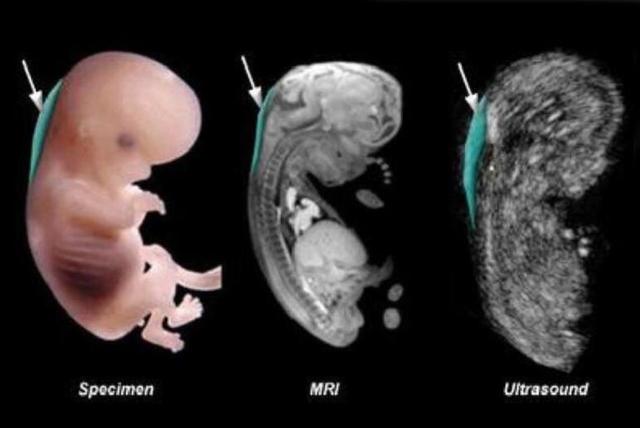

NT检查是通过B超测量胎儿颈项部皮下无回声透明层最厚部位的检查,主要目的是评估胎儿是否患有唐氏综合征的可能。注意,它只是一个评估手段,不能确诊,也就是说即使NT检查不合格,也不能确定胎儿一定有问题。

NT检查对孕周要求非常高,检查太早,胎儿太小,技术上很难实现;检查太晚,胎儿皮下透明带的液体可能被正在发育的淋巴系统吸收,无法得出准确数据。

跟四维彩超一样,NT检查也属于排畸检查的一种,需要胎儿的高度配合。如果胎儿一会儿趴着,一会儿侧着,医生根本无法测量颈部透明层的厚度,检查自然无法顺利进行下去。